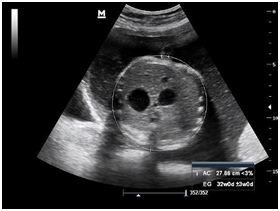

Newborn female was born at 37 weeks 5 days as a product of a second pregnancy, with prenatal diagnosis of duodenal atresia and esophageal stenosis (Figure 1). Due to a previous cesarean section and rupture of the membranes, an emergency caesarean section was performed. Birth weight was 2100 grams APGAR scores were 8–9 at…min. A thoracic-abdominal radiograph was performed, showing thorax without alterations and an image suggestive of duodenal atresia (Figure 2). An echocardiogram CIA 0.5, PCA: 0.2X0.3 showed mild dysplasia of aortic and pulmonary valves. Abdominal laparotomy at 24hours of life, revealed duodenal stenosis secondary to annular pancreas, intestinal malrotation and non-meconium plastic peritonitis without evidence of perforation. The defect was corrected by adhesiolysis, duodeno-duodenal anastomosis and incidental appendectomy.

Figure 1 Prenatal ultrasound: A) image of the double bubble suggestive of atresia/duodenal stenosis (stomach to the left and more centered the duodenum). B) Behind the heart, hyopecogenic image that corresponds to the dilated esophaguss.